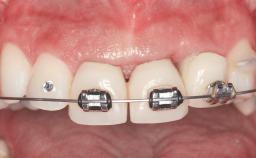

In November 2010, a 44-year-old woman presented to the Harvard School of Dental Medicine seeking options to replace her failing six-unit conventional prosthesis. Having served for approximately 10 years, the fixed partial denture had repeatedly needed recementation after chronic dislodgement over the past few months. Following these episodes, the patient requested further evaluation of her current prosthesis and showed interest in exploring other options for a fixed solution. The patient was in good overall health, presenting with no systemic contraindications to implant therapy or any history of allergies; she did not smoke and was on no medications. Being a well-motivated individual, she regularly saw her general dental practitioner and effectively complied with oral hygiene requirements.